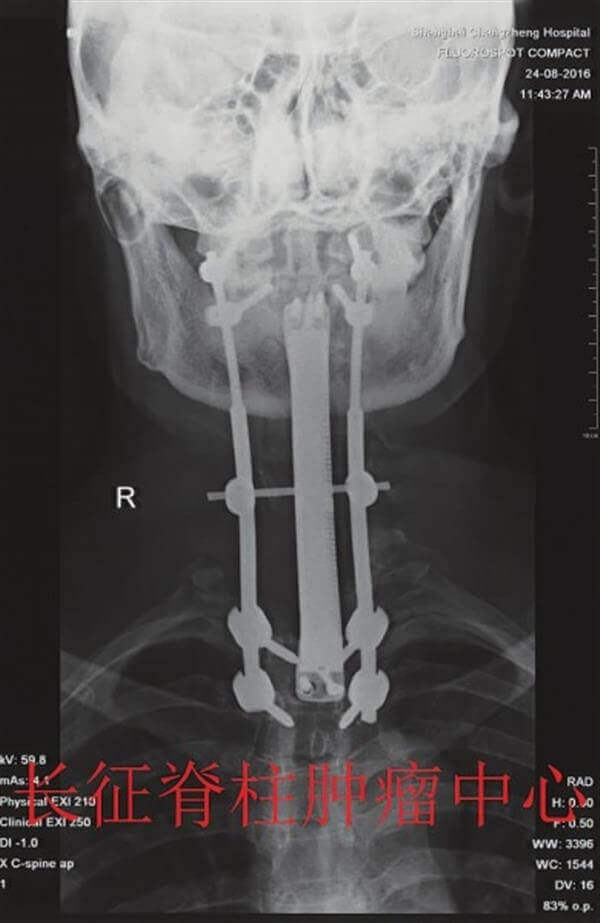

Das 3D-Modell erlaubte ihnen die nächsten Schritte genau zu planen und zu visualisieren. Nach zahlreichen Simulationstests und mechanischen Tests war das Team bereit die Wirbelplatte zu drucken. Das neuartige System ersetzte den Wirbelsäulenabschnitt 6 vollständig. Die Operation dauerte 12 Stunden, in denen die 3D-Wirbel erfolgreich implantiert werden konnten. Die Symptome der Patienten verbesserten sich nach der OP und es traten keine Komplikationen auf. Sie befindet sich nun in einer Reha-Klinik zur Fortsetzung ihrer Behandlung.